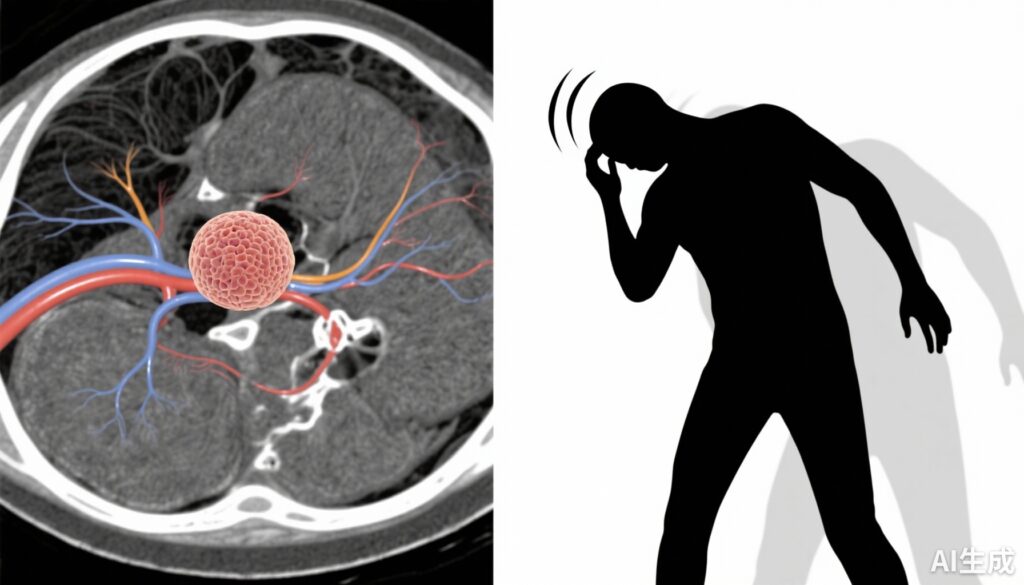

前庭神经鞘瘤(VS),又称听神经瘤,是一种良性、通常缓慢生长的肿瘤,起源于前庭蜗神经的施万细胞。患者常表现为听力下降、耳鸣和眩晕——这些主诉显著影响生活质量。尽管听力下降和耳鸣已得到广泛研究,但VS中眩晕的决定因素和特征仍不太清楚。眩晕可以包括眩晕、失衡或主观不稳,所有这些都会导致残疾和跌倒风险。慢性神经系统疾病中焦虑等心理因素普遍存在,可能调节症状感知和严重程度。确定与眩晕相关的因素可以为更好的症状管理和个性化护理策略提供信息。

这项回顾性队列研究分析了2004年6月至2025年1月期间在华盛顿大学(圣路易斯,密苏里州)接受放射学确诊的109名成年VS患者的数据。所有纳入的患者都完成了前庭功能测试,并使用《眩晕障碍量表》(Dizziness Handicap Inventory, DHI)评估其眩晕障碍,这是一种经过验证的自我报告问卷,评估眩晕的物理、情感和功能影响。焦虑使用《广泛性焦虑障碍-7》(Generalized Anxiety Disorder-7, GAD-7)量表和记录的焦虑障碍病史进行量化。主要结局是眩晕严重程度,定义为连续的DHI评分。多变量分析调整了潜在混杂因素,以确定焦虑测量值与眩晕严重程度之间的独立关联。

该队列的平均年龄为61岁(标准差14),女性占52%。平均DHI评分为27(标准差24),表明轻度至中度的眩晕障碍,但变异范围较大。有焦虑病史的患者平均DHI评分高13.7分(95%置信区间,4.2至23.2),反映更严重的眩晕。值得注意的是,根据GAD-7评分,每增加一个焦虑严重程度点,DHI评分上升2.6分(95%置信区间,2.0至3.3),提示存在剂量依赖关系。在调整了年龄、性别、肿瘤大小和听力损失等协变量后,这种关联仍然存在,每个GAD-7点DHI评分增加1.9分(95%置信区间,1.3至2.6)。平均而言,焦虑病史独立地与10.6分更高的眩晕障碍相关(95%置信区间,2.4至18.7)。这些发现强调了焦虑与VS患者主观眩晕负担之间的重要关联。